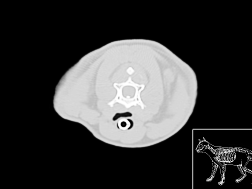

Atlas cérébral du chien IRMT2

IRM T2

>> 17 coupes

Atlas cérébral du chien IRMT1

IRM T1

>> 17 coupes

Atlas cérebral du chien SCTO

Scanner tissu osseux

>> 30 coupes

Atlas cérébral du chien SCTM

Scanner tissu mou

>> 30 coupes